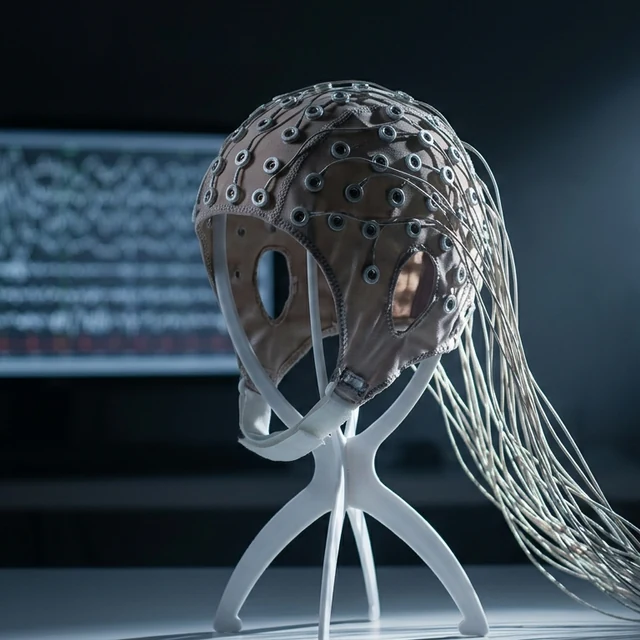

Music Cognition

Gamma · Cognition